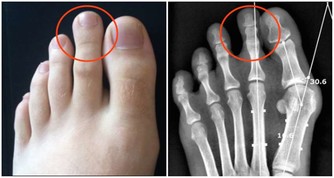

腳上出現這物,竟是心臟病信號。腳部出現青筋腳面部位本來是平坦無皺紋的,如果表面出錢青筋凸起,說明腳部的血液循環開始出現受阻現象。

雖然身體暫時感覺不到其他的不適癥狀,但是我們千萬不可以忽視這一癥狀。